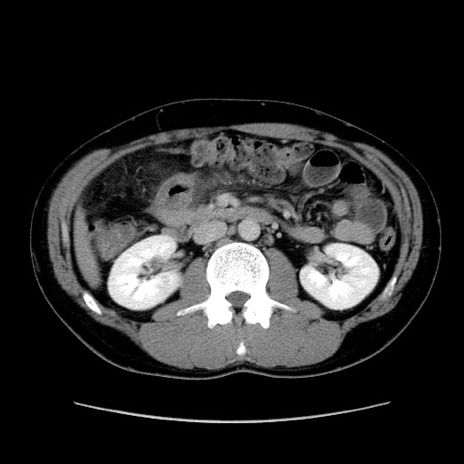

症例36(横断像)

【症例】20歳代 男性

【主訴】心窩部痛

【現病歴】今朝より上腹部痛あり。一旦軽快していたが再度出現したため救急要請。昨日夕に白身の魚を含む刺身を食べた。

【身体所見】BP 136/89mmHg、HR 74/min、BT 37.0℃、腹部:膨満、軟、心窩部に圧痛あり。反跳痛なし、筋性防御なし、腸雑音やや亢進あり。

【データ】WBC 17700、CRP 0.48